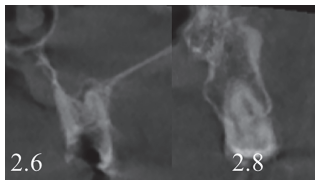

Caso clínico: se presenta el caso de un varón de 28 años, que acudió a consulta por la presencia de unos restos radiculares en localización de primer molar superior izquierdo. Se realizó un autotrasplante dental, siendo el diente donante el tercer molar superior izquierdo, que se trasplantó al alveolo del primer molar, mostrando buena evolución clínica y radiográfi ca.

Clinical case: a clinical case of a 28-yearold man is presented, who went to dental clinic for removal of left fi rst molar roots. An autotransplant was performed using left third molar as donor tooth, which was transplanted into fi rst molar alveolus, showing promising clinical and radiographic evolution.

Por tanto, debido a las altas tasas de éxito descritas en la literatura, el objetivo del presente caso clínico es evaluar clínica y radiográficamente la realización de un autotrasplante con el ápice cerrado, para reponer un primer molar superior izquierdo, como alternativa terapéutica a la colocación de un implante en un paciente adulto.